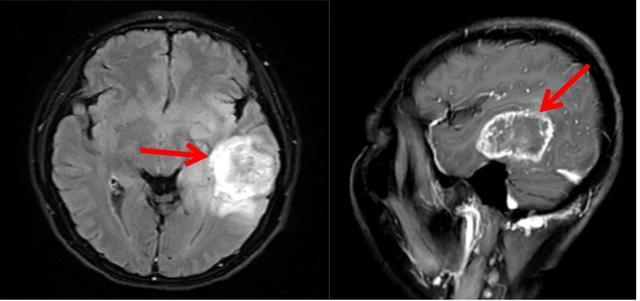

收住院后,匡卫平主任团队对其进行了更细致的头部磁共振检查,确认了肿瘤位于左侧“颞叶”。

匡卫平主任团队对谢阿姨的病情进行了初步的讨论,认为肿瘤位于大脑的“颞叶”,即人脑的语言中枢,这也就解释为什么她明明能听、能看、能说,但就是无法准确描述生活中常见物品的名称及作用,医学上称这种症状为“命名性失语”。